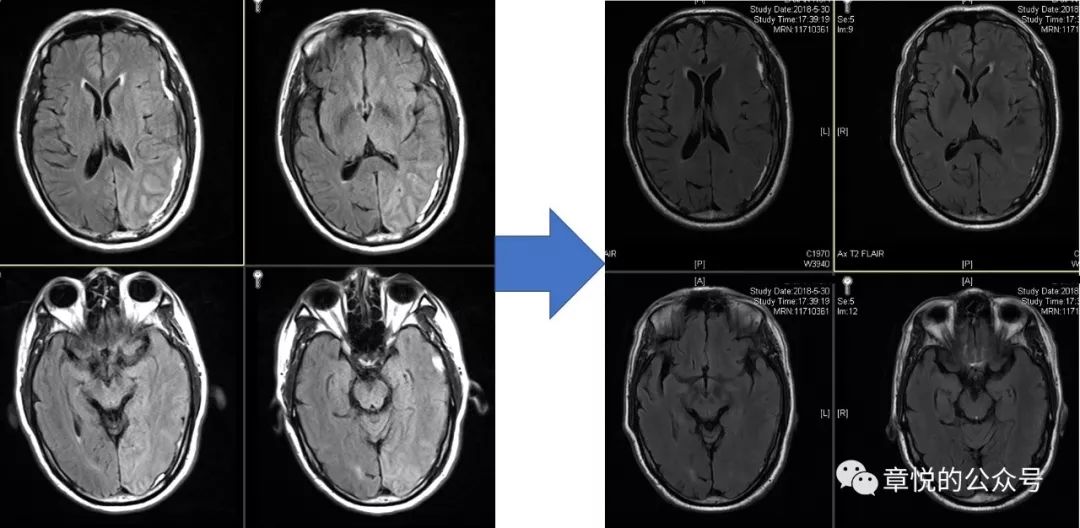

硬膜下脓肿在DWI上信号也很高,这与硬膜下血肿很相似,不过在其他序列上两者有显著差别,近来正好有一例硬膜下脓肿,可以对比一下(图4)。硬膜下脓肿是严重的颅内感染,有高热,大汗淋漓、头痛、血白细胞计数、血沉、C反应蛋白升高等表现,而这些是患者没有的。

图4 硬膜下脓肿和血肿对比,左侧大图为脓肿,右侧半幅小图为血肿,两者T2和DWI比较相似,而T1和FLAIR相差别较大